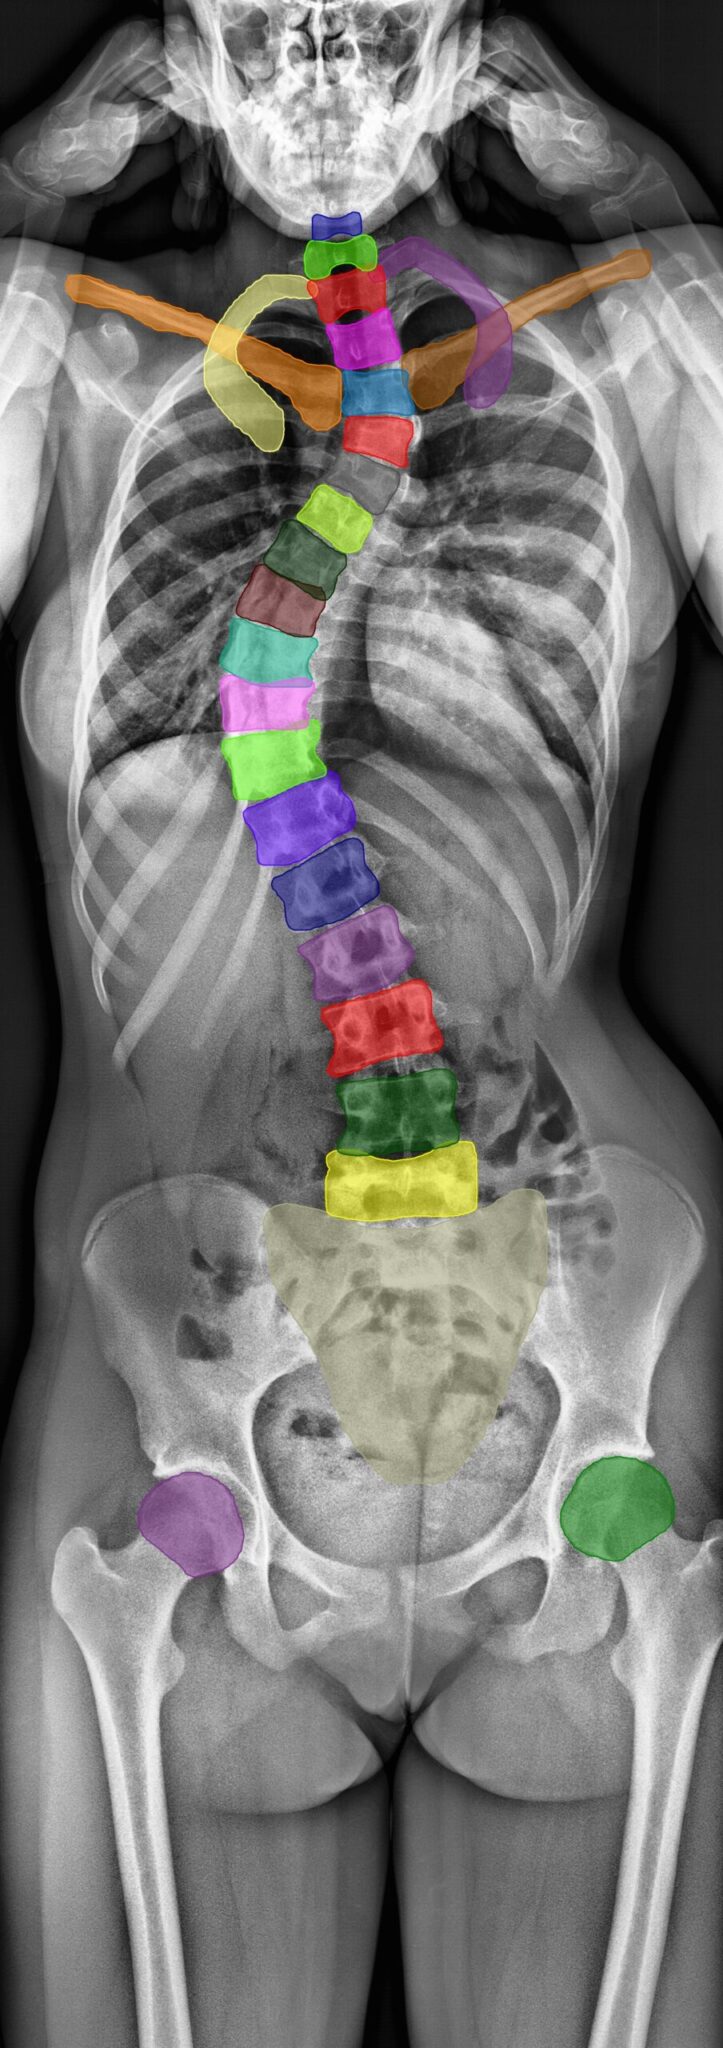

Spinal image analysis for clinical trials, registries, and research.

We have extensive experience designing and executing clinical studies with imaging endpoints for all major spinal therapies, including fusion, motion preservation, and deformity correction—from early feasibility through post-market surveillance.

Our spinal fusion experience spans cervical and lumbar procedures with allograft, autograft, and bioactive implant materials (hydroxyapatite, demineralized bone matrix), utilizing standardized protocols across X-ray, CT, and MRI modalities.

We support IDE, 510(k), and PMA submissions with regulatory-grade measurements of fusion status, segmental motion, alignment, subsidence, and device performance—all delivered with faster turnaround and seamless EDC integration compared to traditional core labs

Spine

Can artificial intelligence support or even replace physicians in measuring sagittal balance? A validation study on preoperative and postoperative full spine images of 170 patients // read more

The FDA-approved Functional X-Ray Analysis software (FXA) of our imaging core lab is capable of automatically evaluating over 150 radiographic parameters of the spine, hip, or knee. The reproducibility of the measurements is on file with FDA 510(K).

Explore some of our most popular automatically assessable quantitative radiographic parameters below.

Range of Motion (RoM)

The Angular Motion/Range of Motion (RoM) is a quantitative parameter used to evaluate spinal fusion.

It is measured as the angular difference of two adjacent vertebrae during the flexion and the extension posture of a patient and is reported as an absolute value in degrees (°). RAYLYTIC’s FXA software has been shown to measure RoM 15 times more precisely than experienced physicians (Schulze et al., J Biomech 2011).